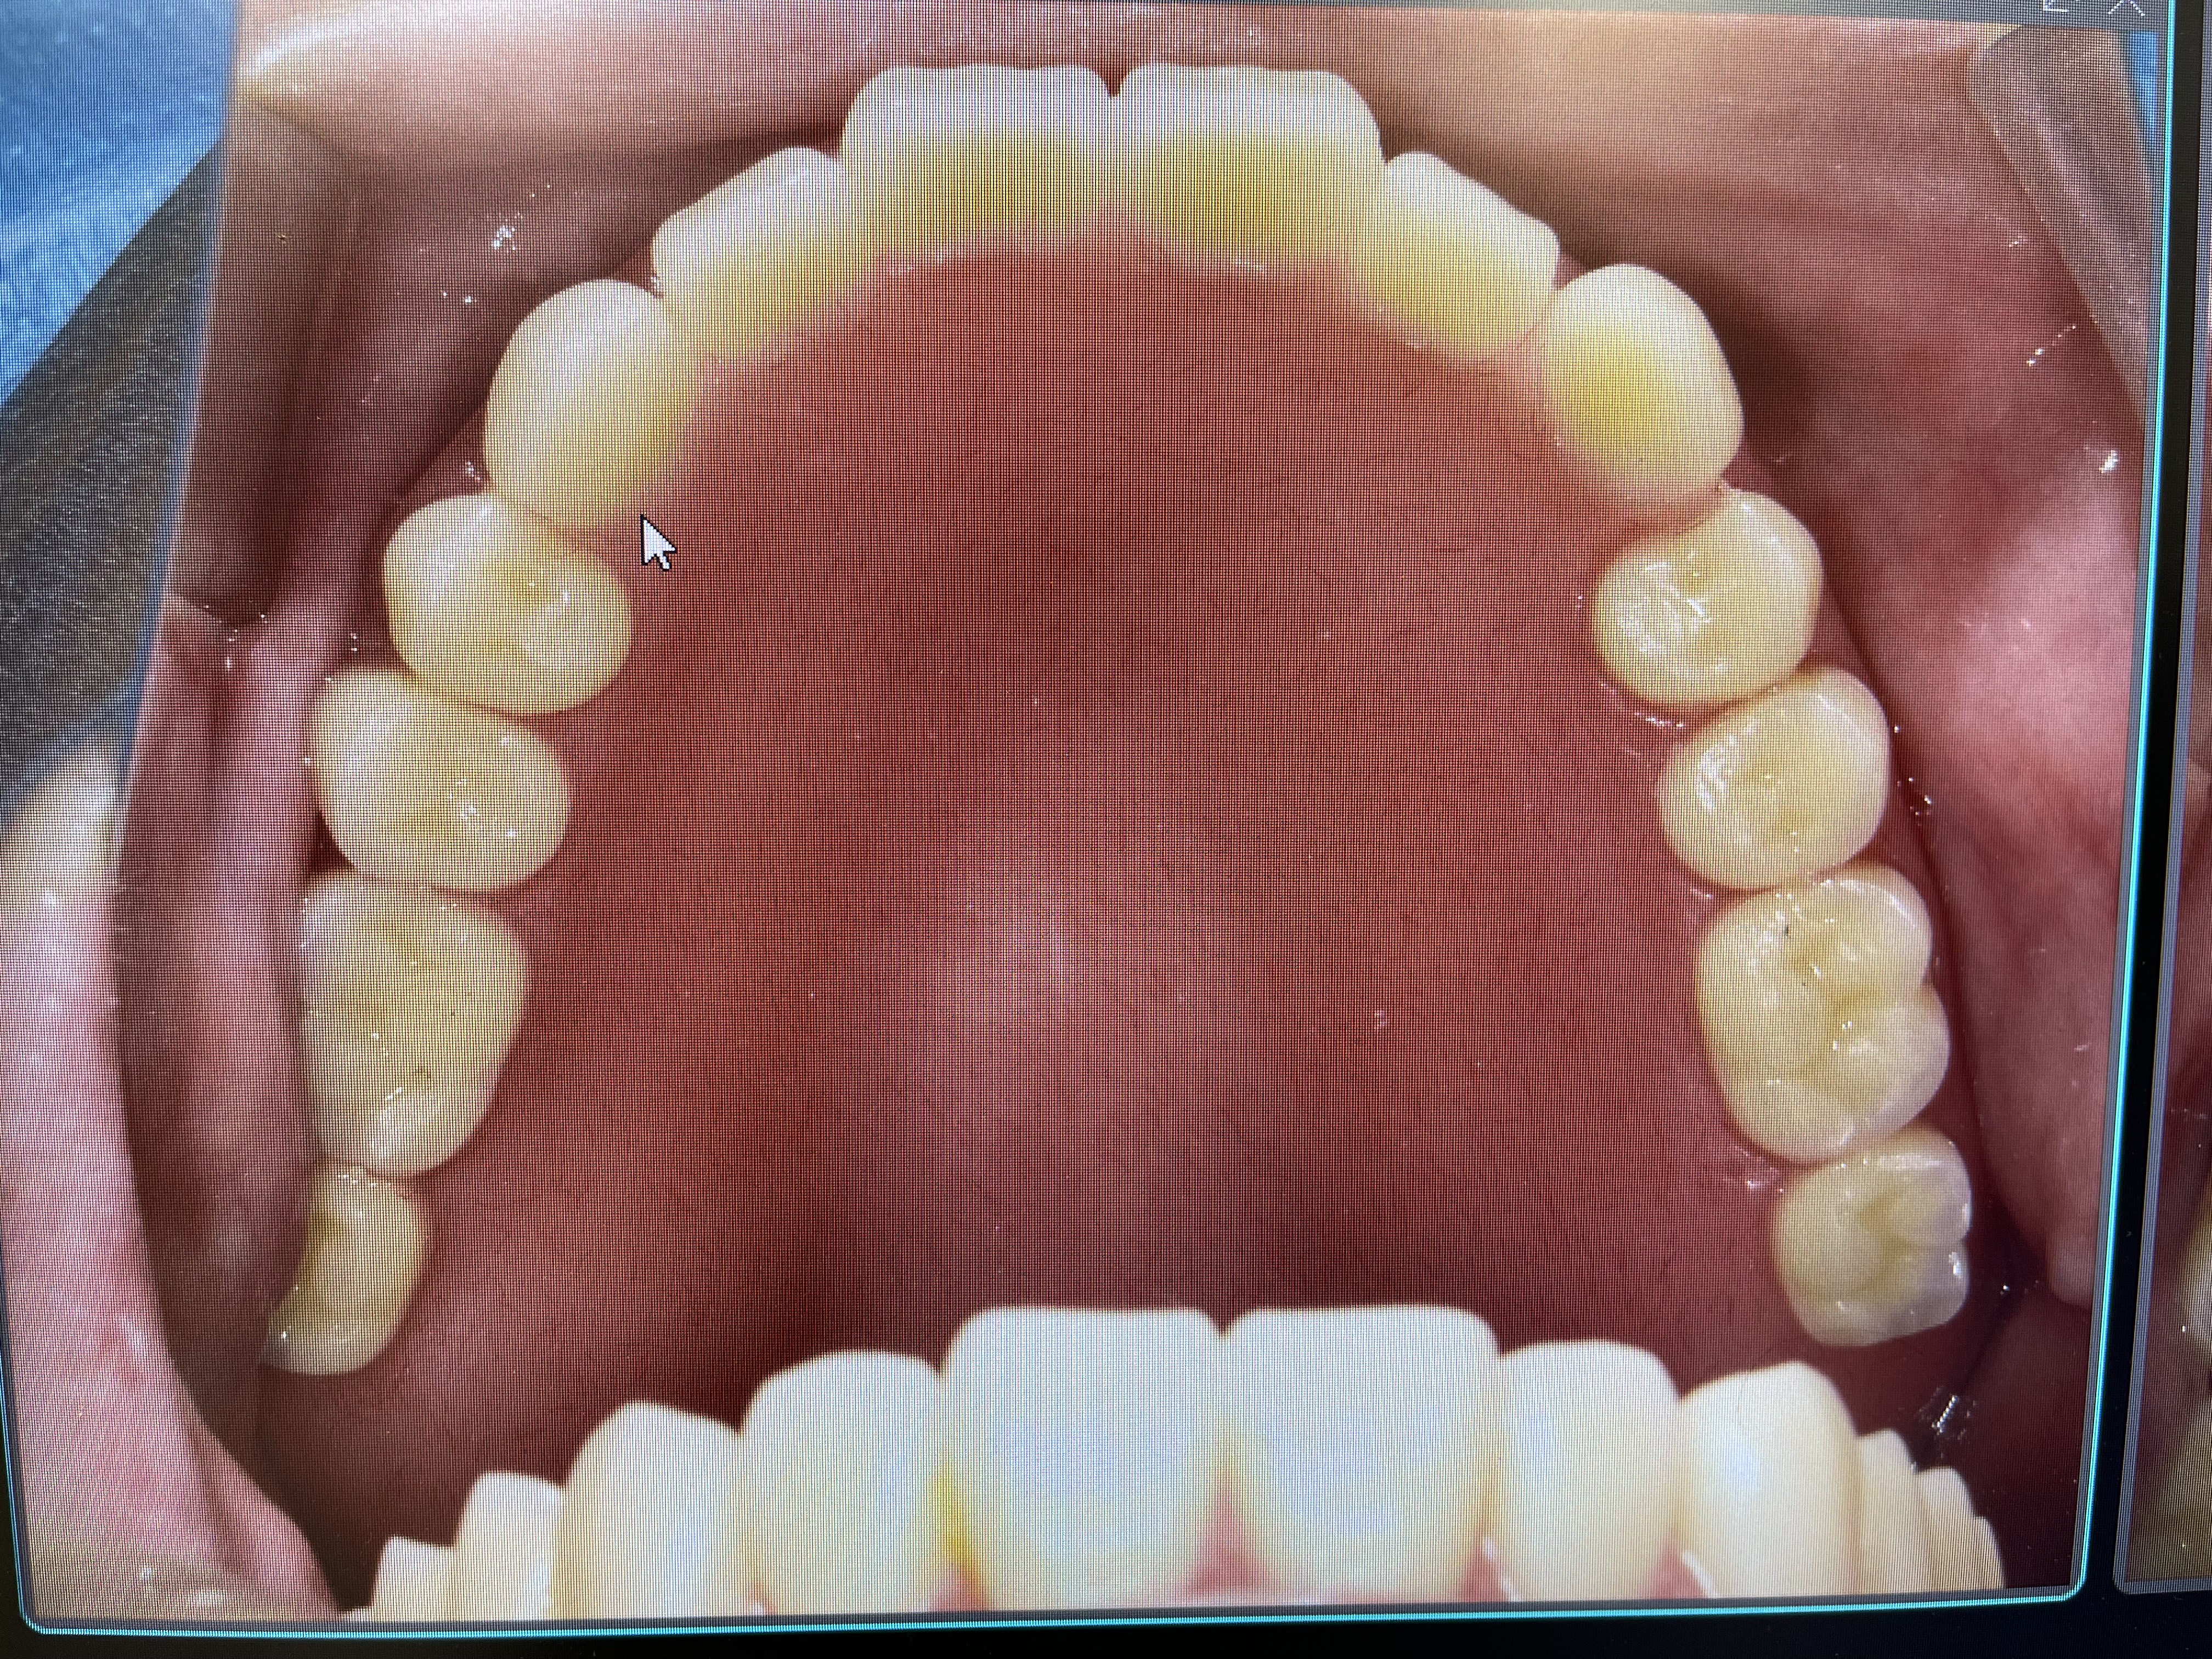

Title ” 総義歯の患者様のインプラント症例”

2024年暮れ、義歯(入れ歯)の痛みで

食事ができない患者様(75歳)が来院されました。

今までにたくさんの歯科医院を渡り歩き、

それでもなお痛みが取れず、

通われていた病院からの紹介で和田歯科医院に来られました。

診察をしたところ、下顎の骨の痩せ方が著しく

義歯(入れ歯)が安定しにくいため

固定式のインプラントを提案しました。

固定式のインプラントをすることで、

上顎も外れない安定した総義歯になるということです。

下顎インプラントを4本埋入した状態

インプラントが4本埋入した下顎模型

下顎インプラント模型に仮歯が入っている状態

上部構造が入っている状態(下顎パノラマ写真)

下顎口腔内に最終補綴物(被せ物)が入っている状態

上顎総義歯&下顎インプラントブリッジが入っている状態(口腔内写真)